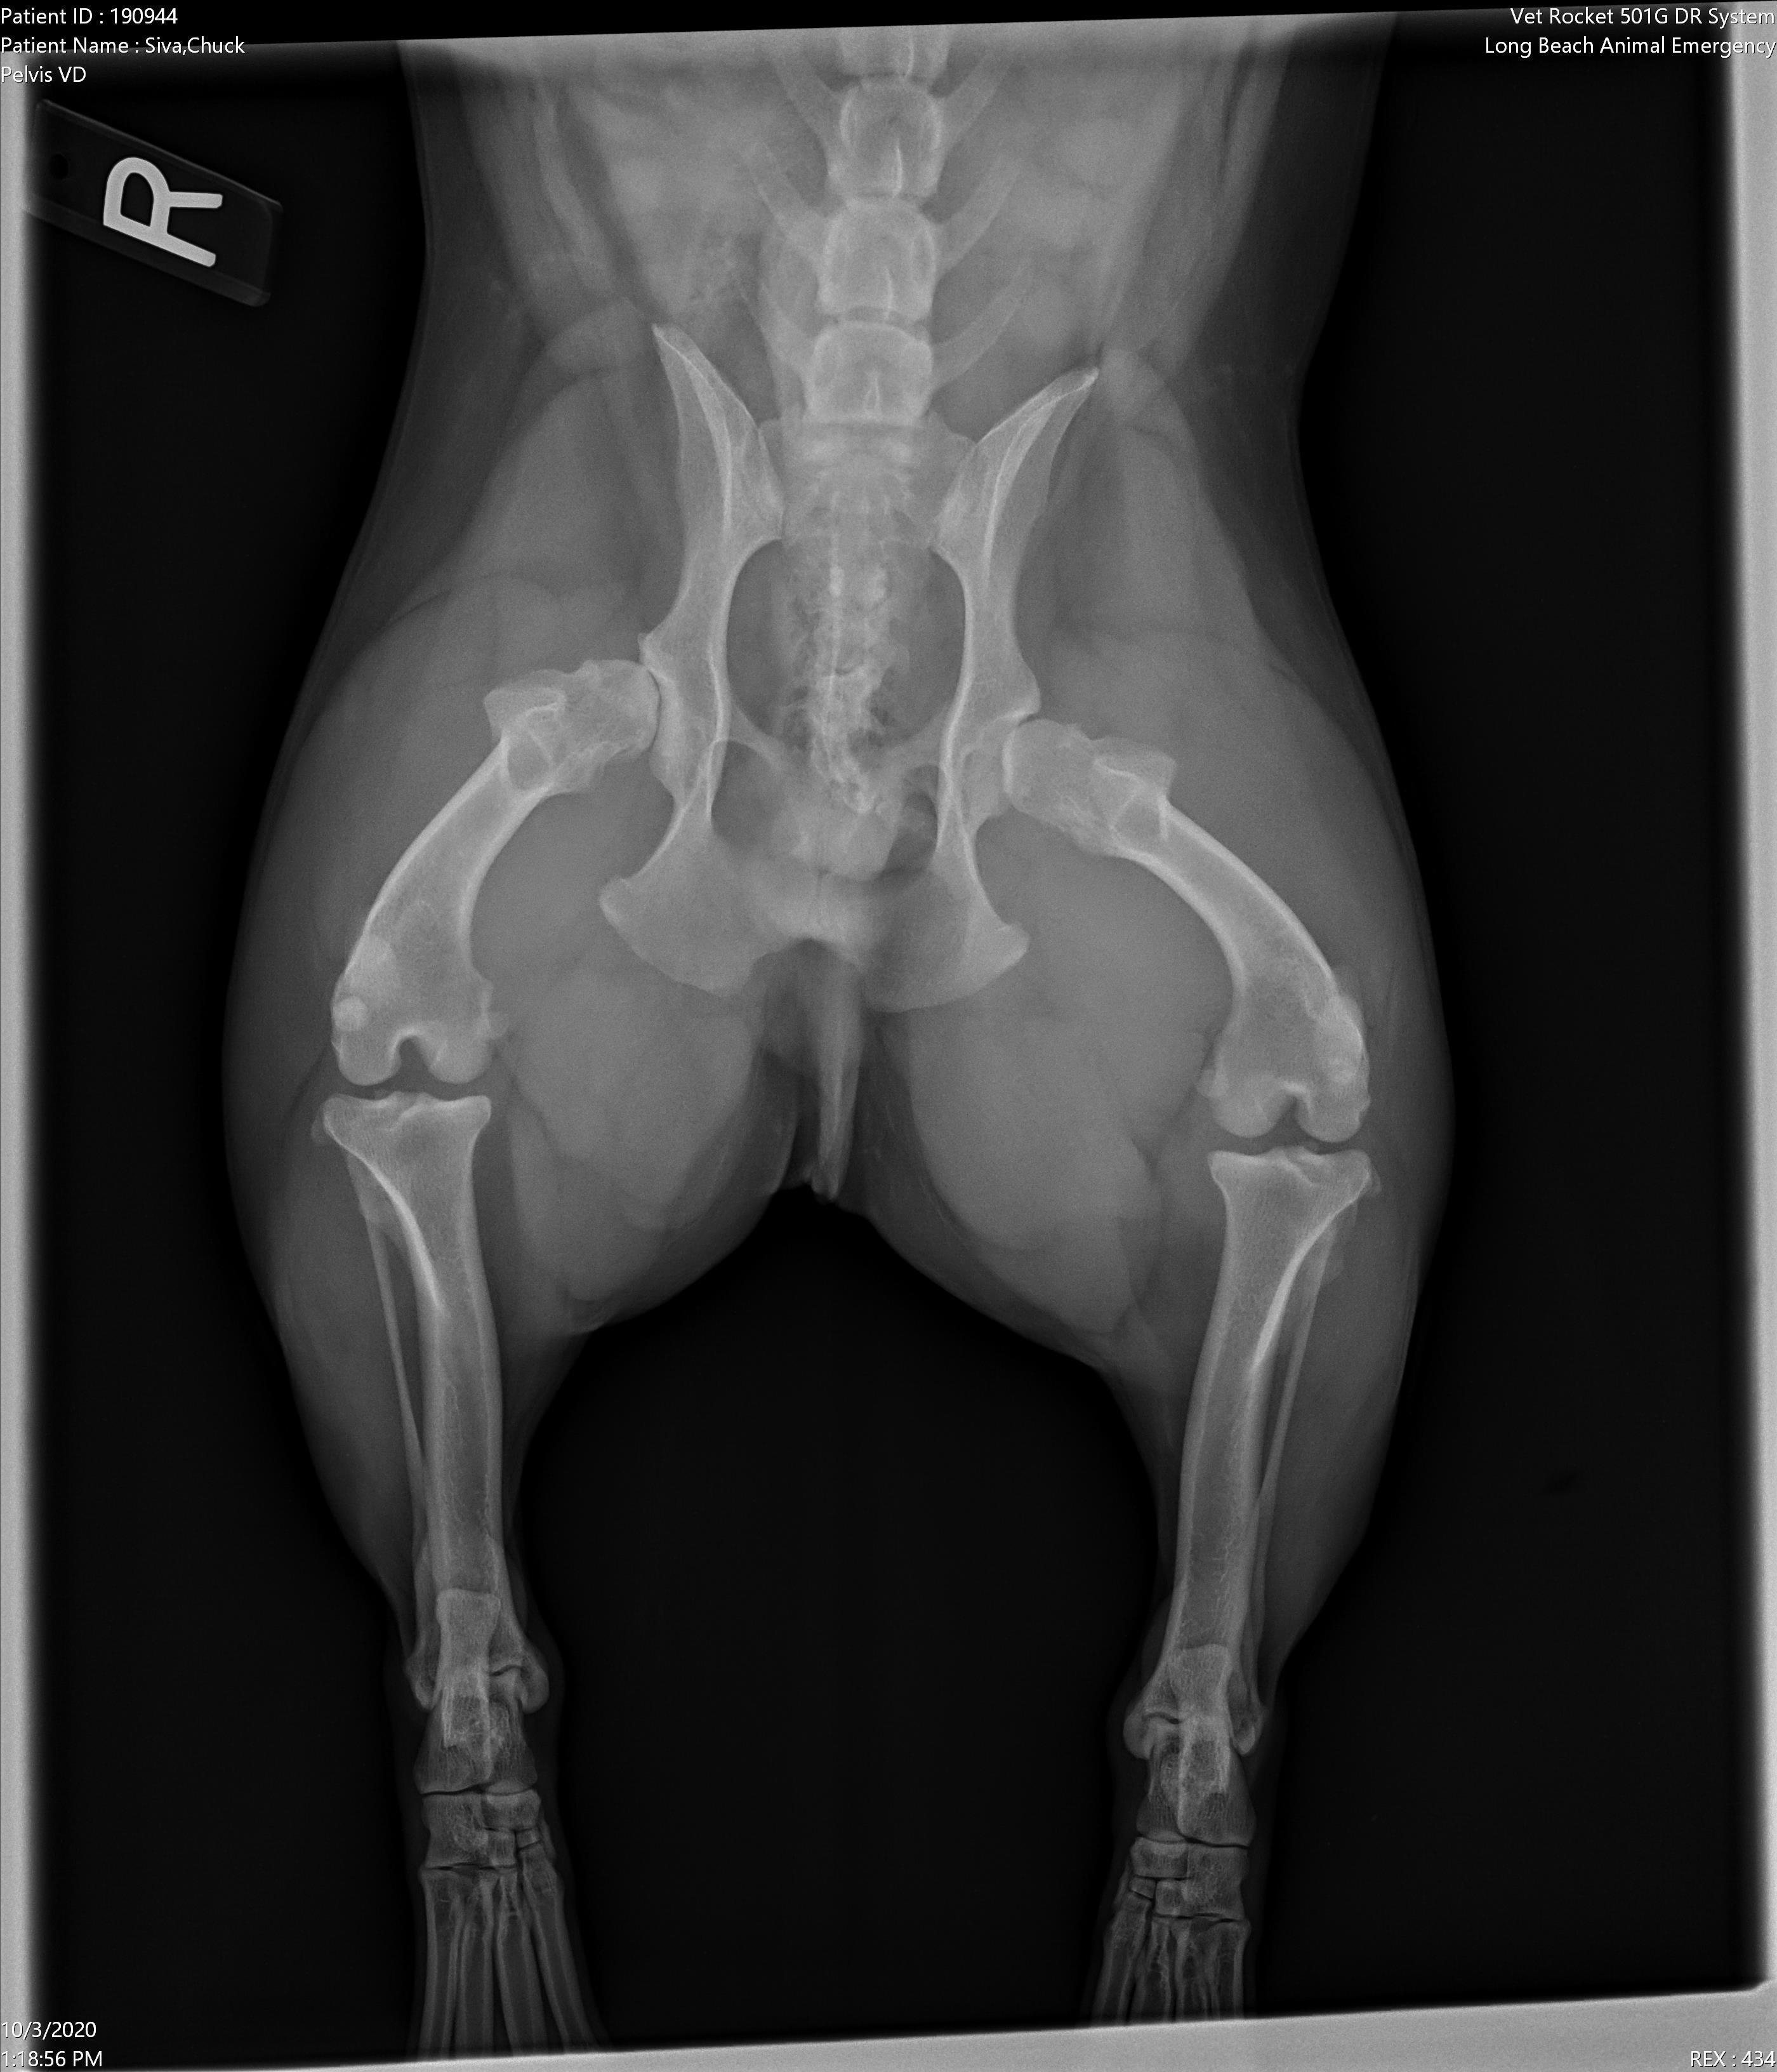

Pet's info: Dog | French Bulldog | Male | neutered | 5 years and 9 months old | 29 lbs

Hi! My 5 1/2 year old French Bulldog was taken to the emergency bc we noticed his leg was hurting him and started to pant and panic. The emergency vet told us that was the least of our worries and proceeded to tell us he had a brain injury even though it was all assumption and wanted us to put him down! This place is a scam! I demanded an X-ray and he is better now back at home but still need to treat his leg. Can you tell me if this hip displaisia, dislocation, arthritis or a fracture?

Poor guy. Your pet Chuck has severe hip dysplasia and possibly even early signs of arthritis. It is so severe that the femoral head doesn't even appear to be in the socket, creating a subluxation appearance as well. I would highly recommend having your vet send Chuck to an orthopedic specialist to get a treatment plan to help stabilize these joints for Chuck so that he does not succumb to a permanent debilitated state due to this defect. I am so sorry that you had to go through so much with your pet and I am glad that his condition is at least stable for now. Here is more information on hip dysplasia in dogs and some of the procedures that can be done to help manage this condition--> https://veterinarypartner.vin.com/default.aspx?pid=19239&id=4952203 Best of luck with Chuck moving forward and I hope that you are able to manage his hip dysplasia condition well. Take care.